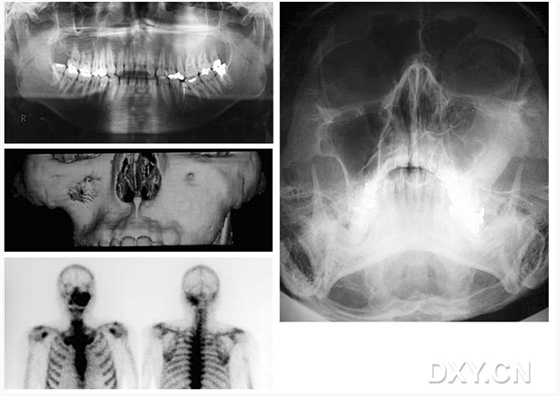

骨肉瘤